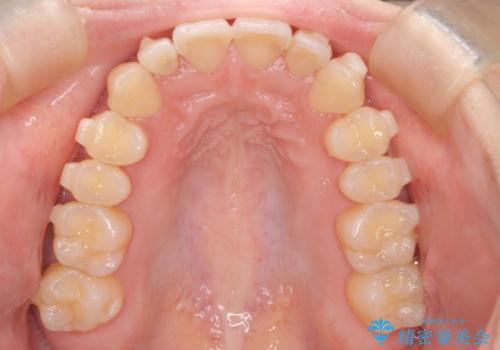

【インビザライン】反対咬合を治したい

- 前歯の反対咬合を主訴に来院されました。

インビザラインにて歯列弓の拡大により叢生の改善を行うことができ、患者様にも満足していただました。